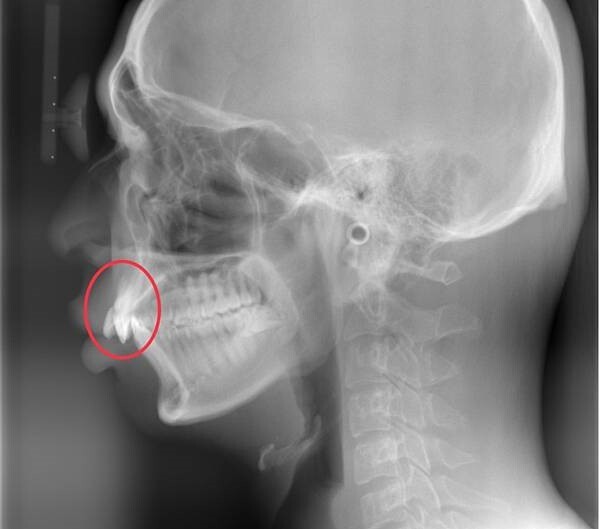

第五種是暴牙或小下巴,多數人都會以為這二種情況完全不同、很容易辨識,今年就收治了一名大學生,主訴自己有暴牙,但她診斷發現門牙的角度並沒有往前突,反而是角度過直,因而從小限制了病患下顎骨往前生長,導致下巴過於後縮,後縮的小下巴讓門牙顯得突出,才讓病患自以為是暴牙而錯怪了門牙十幾年,也錯過治療的最佳時機。醫師提醒,特別是上下顎發育的問題,一定要把握兒童上下顎骨各自的生長高峰期,藉由專業矯正醫師介入治療,否則一旦錯過了這段時機,就容易造成較嚴重的骨性齒顎不正。

錯怪暴牙十幾年,原因竟是下顎發育受限,迫使下巴生長短小